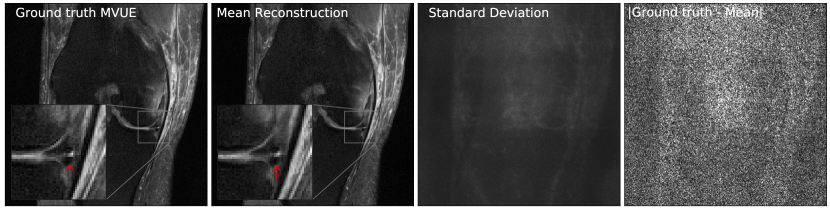

Refer to caption

Figure 4: Our method successfully recovers fine details and can provide an estimate of the reconstruction error. The left column shows a knee from the fastMRI dataset, along with an annotated meniscus tear (indicated by red arrow in zoomed inset). Given measurements at an acceleration factor of R=4𝑅4R=4, we obtain 484848 independent reconstructions via posterior sampling. The second column shows the pixel-wise average of reconstructions, the third column shows the pixel-wise standard deviation, and the fourth column shows the magnitude of the error between the ground truth and the mean reconstruction. Note that our generative prior has never seen such pathology, as it was trained on T2-weighted brain scans.

4.3 Uncertainty Estimation

Our method can also provide uncertainty estimates for each reconstructed pixel by running multiple reconstruction samplers. For a given observation y𝑦y, we can obtain independent samples x^1,,x^Kμ(|y)\widehat{x}_{1},\cdots,\widehat{x}_{K}\sim\mu(\cdot|y), for K𝐾K sufficiently large. Now, using the conditional mean estimate x¯=i=1Kx^i/K¯𝑥superscriptsubscript𝑖1𝐾subscript^𝑥𝑖𝐾\bar{x}=\sum_{i=1}^{K}\widehat{x}_{i}/K, we can compute the pixel-wise standard deviation i=1K|x^ix¯|2/Ksuperscriptsubscript𝑖1𝐾superscriptsubscript^𝑥𝑖¯𝑥2𝐾\sqrt{\sum_{i=1}^{K}|\widehat{x}_{i}-\bar{x}|^{2}/K}, and this gives an estimate of the error in each pixel. As shown in Fig 4, the pixel-wise standard deviation is a good estimate of the ground truth error |xx¯|superscript𝑥¯𝑥|x^{*}-\bar{x}|. Additionally, notice that the reconstructions are able to recover fine details such as the annotated meniscus tear222https://discuss.fastmri.org/t/219 in Fig 4 and predict low uncertainty for these features.

Figure 17 in Appendix D shows another example of an annotated meniscus tear. Figures 18 and 19 show comparisons with baselines on the same examples.